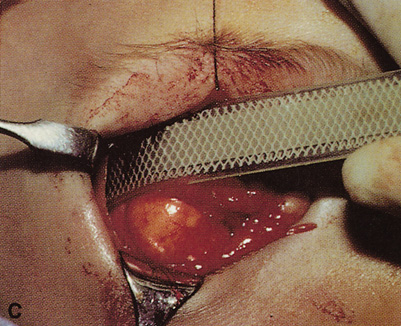

wall still can be carried out. | Fig. 9. A,B. Coronal and axial CT images of a large intraconal neoplasm. C. Because it was felt to represent a well-encapsulated cavernous hemangioma, this

lesion was a candidate for removal via an eyelid crease orbitotomy

without bone removal. The eyelid crease incision marked. D. Incision made with scalpel. E. Orbicularis muscle is tented up and incised to expose the underlying septum. F. Dissection of a skin-muscle flap deep to orbicularis exposes the orbital

septum and superior orbital bony rim. G. Cutting cautery is used to incise periosteum along the superior and lateral

rims; finger palpation of the bone helps to direct this incision. H. Periorbita is elevated along the mesial surface of the lateral orbital

rim in order to expose the deep orbital tissues. I. The cavernous hemangioma is visualized in the wound. Retraction is provided

by one or more malleable retractors. J. Cryoprobe is affixed to the hemangioma to facilitate manipulation of the

lesion. K. Large cavernous hemangioma after removal through the eyelid crease incision

which was accomplished without bone removal. L. Periorbita is reattached over the lateral rim. M. The eyelid crease incision is closed with a running suture. |